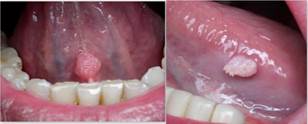

En los 17 pacientes diagnosticados con infección del VPH se encontró que la lesión elemental más frecuente fue la verrugosidad (70,5%), luego la vegetación (23,5%) y manchas y placas (5,8%). (Tabla 3) (Figura 3).

Acerca de las lesiones características reportadas en cavidad bucal se encuentran las lesiones verrugosas, vegetativas y pápulas, generalmente asintomáticas, relacionadas con prácticas sexuales oro-genitales. El condiloma acuminado es el tipo de lesión más frecuentemente reportado. Los tipos más relacionados con lesiones bucales son los 16, 18, 13 y 32, estos 2 últimos, asociado a la hiperplasia epitelial focal (Enfermedad de Heck)15. El tratamiento para dichas lesiones depende de la severidad y progresión de la infección. En las mucosas, se recomienda la extirpación quirúrgica, y la aplicación de ácido tricloroacético; que ha demostrado grandes resultados sin recidiva en pacientes con hiperplasia epitelial focal16.